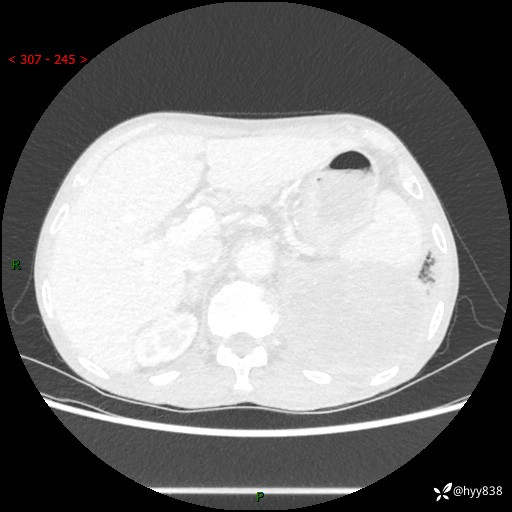

77岁/男,腹痛2月,CT发现左肺占位1天。巨大肿块,肺内或肺外来源…结果公布~

主诉:腹痛2月,CT发现左肺占位1天

现病史:患者于2025年9月间断左下腹胀痛,在当地镇卫生院行彩超检查考虑泌尿系结石,行止痛排石对症治疗未见明显好转;1天前腹痛症状加重,至当地市第三人民医院行CT检查:左肺下叶巨大团块状软组织影,考虑肿瘤性病变,建议增强CT检查;左侧胸腔积液;纵膈内淋巴结肿大;双肺肺气肿;右肺中叶纤维灶。为进一步求治,来我院就诊。

胸部CT平扫+增强